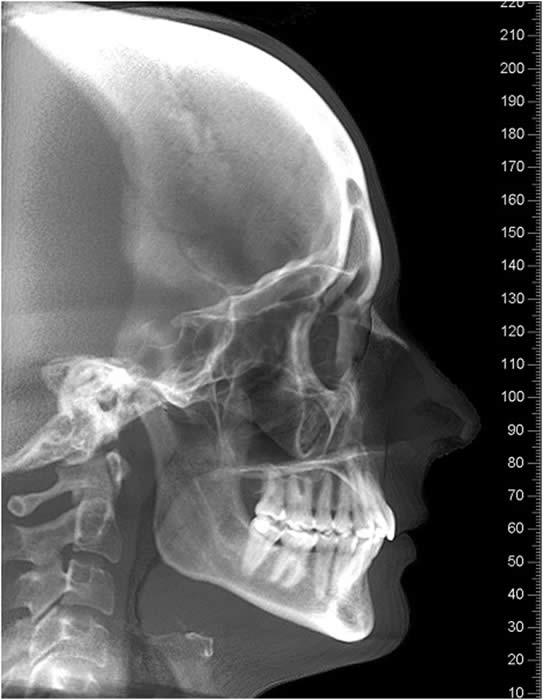

Other Plain Film Views The lateral cephalogram and the posterior-anterior cephalogram are routinely used by orthodontists and are useful in assessing skeletal relationships and facial asymmetry but are not of value for information about the TMJ diagnosis because of superimposition .